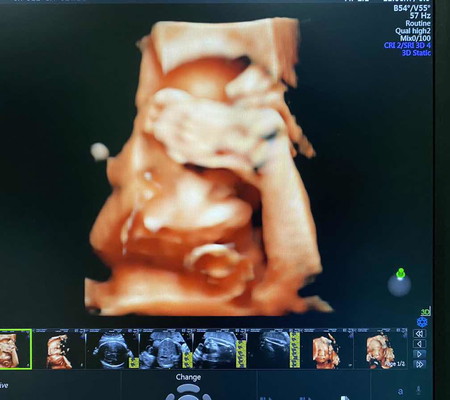

-ไม่ต้องเอาทีนก่ายหน้าลูก .. หมอบอกอ้วนได้อีก ? #ประชดป่าววุ้ย ... แม่เพิ่ง 32w2d ตัวหนูไปเป็นเด็ก 35w แล้ว 2269g เองลูก จาก 2 อาทิตย์ที่แล้ว 1763g ? ป้าหมอบอกชอบเด็กอ้วนลูกไม่เป็นไร ยังไงแม่กะพ่อก็รัก ❤️ #ตุ้ยนุ้ยของแม่ #ถีบเก่ง #อยากเจอแย่แล้ว

กำลังจะเป็นแม่